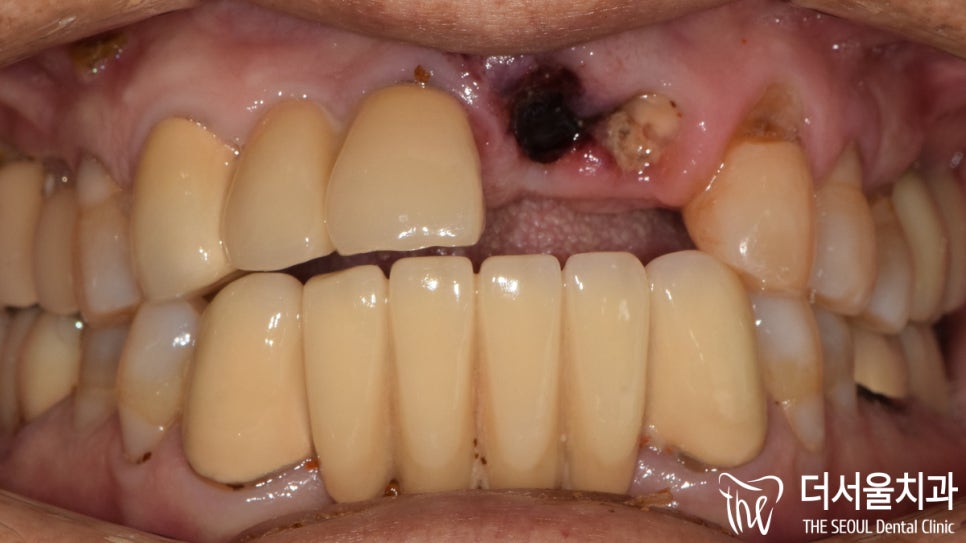

이분께서 앞니가 부러져서 빠졌다고 오셨기에

말씀하신 내용을 토대로 확인을 했습니다.

어.. 한 군데가 아닌,

왼쪽 앞니 두 곳에 부러짐이 나타나 있네요.

이와 더불어,

주변에 있는 치아들도 상황이 좋지 않았습니다.

아무래도 단순히 부러진 것이 아니라는 판단이 들어

정확한 진단을 위해 엑스레이 촬영을 진행했습니다.